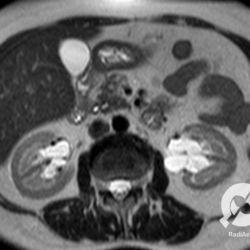

Avaliar um pouquinho, vamos mostrar uma ressonância magnética. As características de uma lesão no mudam: septos, vegetações, captação de contraste... E o nosso caso aqui é de um cisto multisseptado, com septos levemente espessos e sofrendo impregnação pelo meio de contraste localizado no terço médio do rim direito. Classificação de Bosniak III, com alta possibilidade de representar neoplasia maligna.